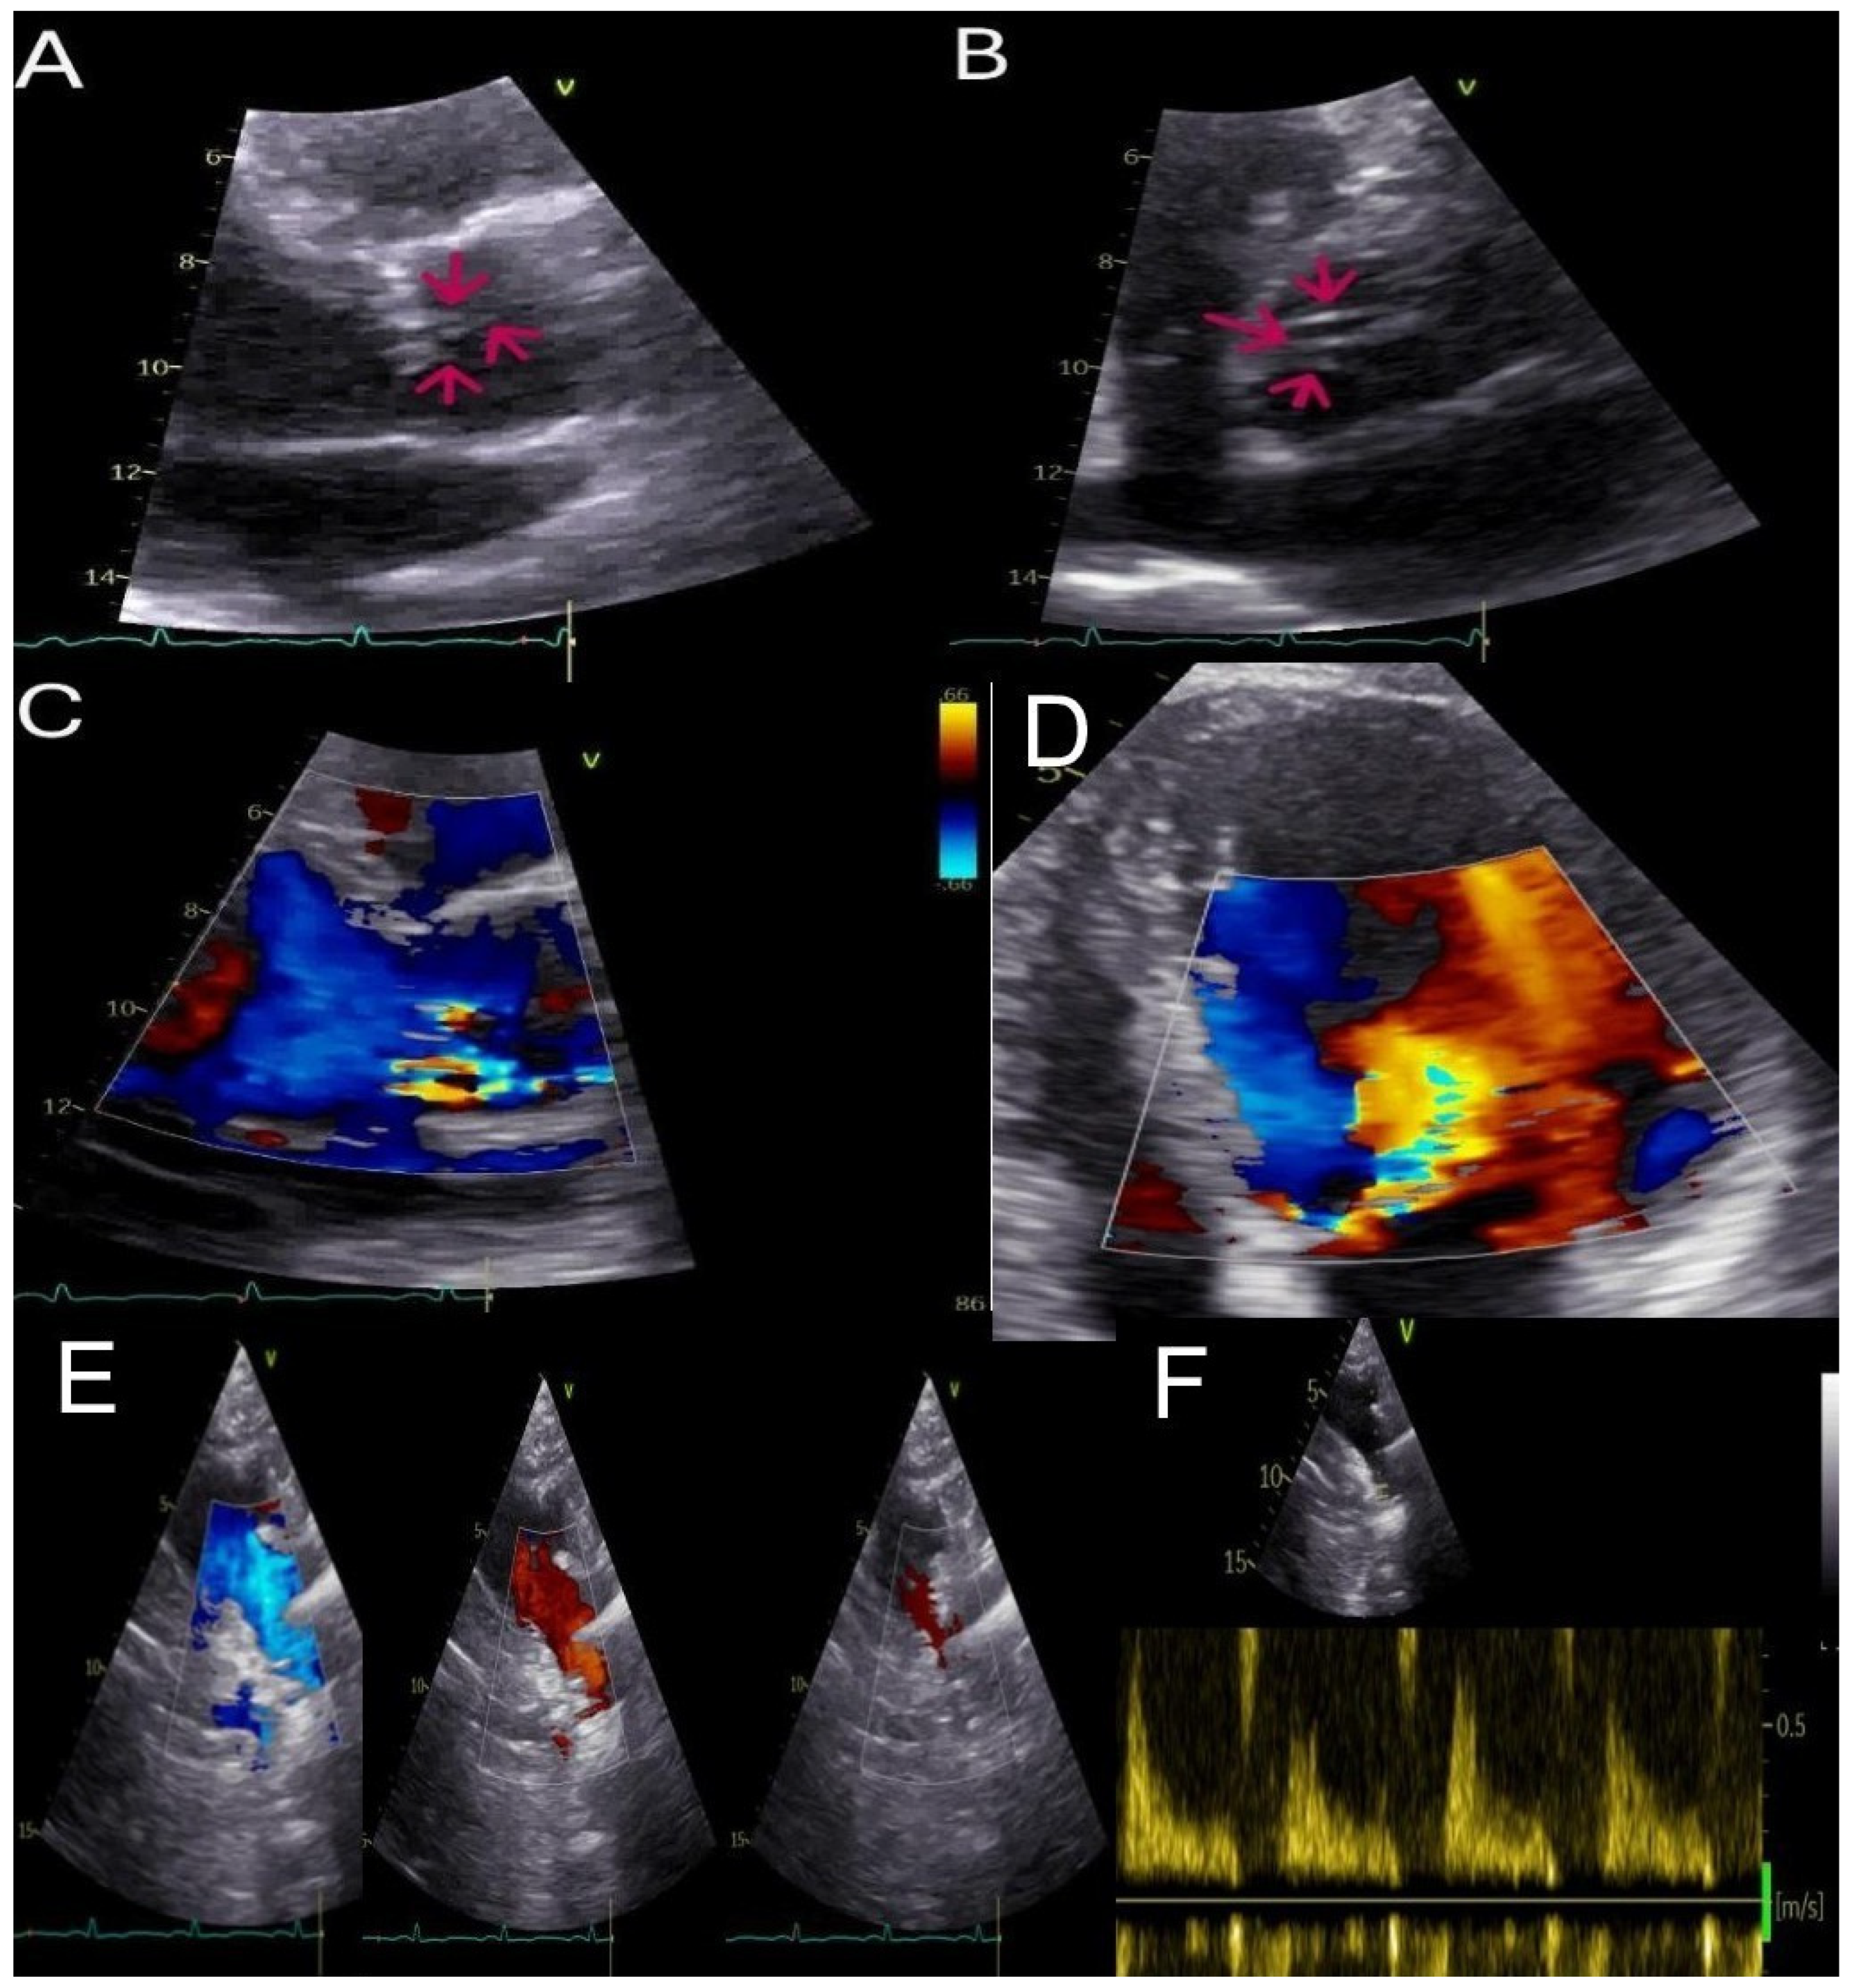

A Rare Case of Severe Aortic Regurgitation Secondary to Tenting of Chordae Tendineae Strands: A Multimodality Imaging Approach for a Challenging Diagnosis